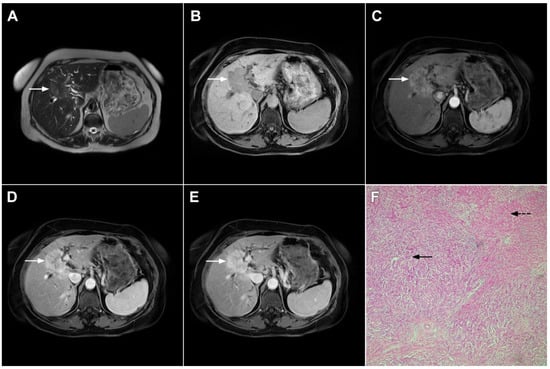

Ancillary MRI findings that are frequently seen in mICC include peripheral biliary dilatation, capsular retraction, vascular encasement, lobar atrophy, satellite nodules, and lymphadenopathy [15,16]. Nevertheless, it should be kept in mind that in the parenchymal type of mICC, due to its origin from the small bile ducts, ancillary features such as biliary dilatation, vascular encasement, and lobar atrophy may be absent (Figure 5). In such cases, the presence of typical postcontrast behavior and capsular retraction indicate mICC. On the other hand, some degree of obstruction and peripheral bile duct dilatation is always seen in the ductal type of mICC [15].

Figure 5.

Parenchymal mass-forming cholangiocarcinoma in a 36-year-old man. The lobular slightly hyperintense lesion (arrow) is seen in the liver segment IVA in a T2-weighted image (A) with subtle capsular retraction (dashed arrow). On a plain T1-weighted image (B), the tumor (arrow) is hypointense with irregular discrete peripheral and central enhancements in the arterial phase (C), mild progressive enhancement in the portal venous phase (D), and high signal intensity in DWI (E). Hematoxylin and eosin (H&E) staining (F) showed cholangiocarcinoma (arrowhead) with poorly differentiated components (dashed arrow). Normal liver parenchyma is also shown (arrow); original magnification ×40.

2.2. Atypical Imaging Features of mICC

Besides the typical imaging presentation of mICC, atypical appearance can also be observed in imaging studies [24]. Hypervascular mICCs are usually small lesions and this vascular behavior might be explained by less intralesional fibrosis and abundant vascular stroma [25]. The incidence of hypervascular mICC ranges from 12.5% up to 47% in previous reports [18,25]. Since hypervascular mICCs are frequently seen in cirrhotic livers, the differential diagnosis with HCC may be very difficult. In this regard, the absence of washout and the presence of progressive enhancement together with the lack of fibrous pseudocapsule favor the diagnosis of mICC over HCC [25]. However, if hypervascular mICC shows washout in the portal venous phase, preoperative differential diagnosis with HCC is hardly possible (Figure 6). In such cases, additional findings, such as cloud appearance in the hepatobiliary phase, multiplicity around the main tumor, or intrahepatic metastasis, capsule retraction and tumor markers may be helpful for differentiating between these tumors [18,19]. Hypervascular mICC differs from typical hypovascular mICC not only in terms of vascularity but also in patient outcome, as it has been shown that the former has much better prognosis [12]. Therefore, the assessment of tumor vascularity on preoperative imaging could represent an important marker for predicting malignant characteristics in mICC [26].

Figure 6.

Hypervascular mass-forming cholangiocarcinoma in a 63-year-old woman. The axial T2-weighted image (A) shows a moderately hyperintense tumor (arrow) located in liver segments VI and VII with a subtle medial capsular retraction. The lesion (arrow) is hypointense on the plain T1-weighted image (B), hypervascular in the arterial phase (C) with washout on the portal venous phase (D). The tumor (arrow) is hyperintense on DWI (E). Hematoxylin and eosin (H&E) staining (F) showed well-differentiated cholangiocarcinoma (arrow) surrounded by normal liver parenchyma (dashed arrow); original magnification ×40.